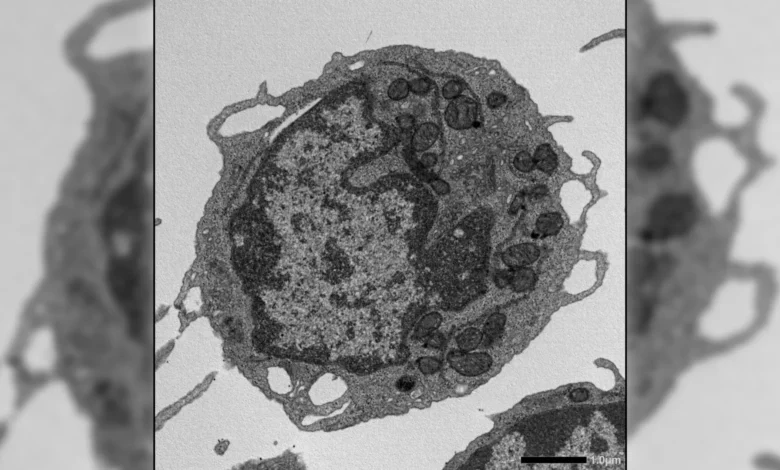

When activated by various forms of cellular stress, MLKL exhibited a remarkable transient translocation to the mitochondria. Once associated with these vital organelles, MLKL initiated a cascade of detrimental effects. It was observed to reduce mitochondrial membrane potential, a critical indicator of mitochondrial health and energy generation efficiency. Furthermore, MLKL activation led to structural alterations within the mitochondria, compromising their integrity, and significantly impaired their ability to produce adenosine triphosphate (ATP), the cell’s primary energy currency. These mitochondrial dysfunctions, occurring without outright cell death, proved to be the underlying drivers of key aging phenotypes in HSCs. Specifically, they resulted in a diminished capacity for self-renewal, a reduced output of lymphoid cells essential for adaptive immunity, and a pronounced skewing of differentiation towards myeloid cell lineages, contributing to the age-associated imbalance in the immune system.